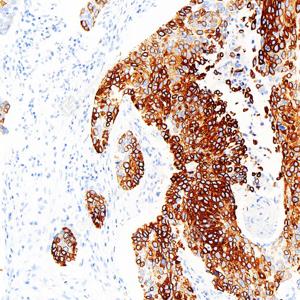

IHC检测Cytokeratin 15蛋白(货号 GB150044). 样品: 人肺鳞状细胞癌, 4%多聚甲醛 (货号G1101) 固定12-24小时. 抗原修复: Tris-EDTA抗原修复液(pH 9.0) (G1203), 98℃, 20分钟. —抗: 1: 1500稀释, 4℃ 孵育过夜. 二抗: S-vision免疫组化多聚二抗(山羊抗兔),即用型 (货号G1302), 室温孵育20分钟. |